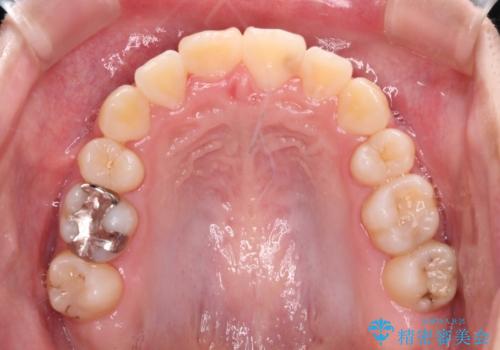

八重歯で正中が右にずれている ワイヤー装置での抜歯矯正で正中位置を改善

正中位置の改善に時間がかかることが予想され、2年半を治療期間の目標としておりましたが、20歳と年齢が若いこともあり、2年2ヶ月で治療を終えることができました。